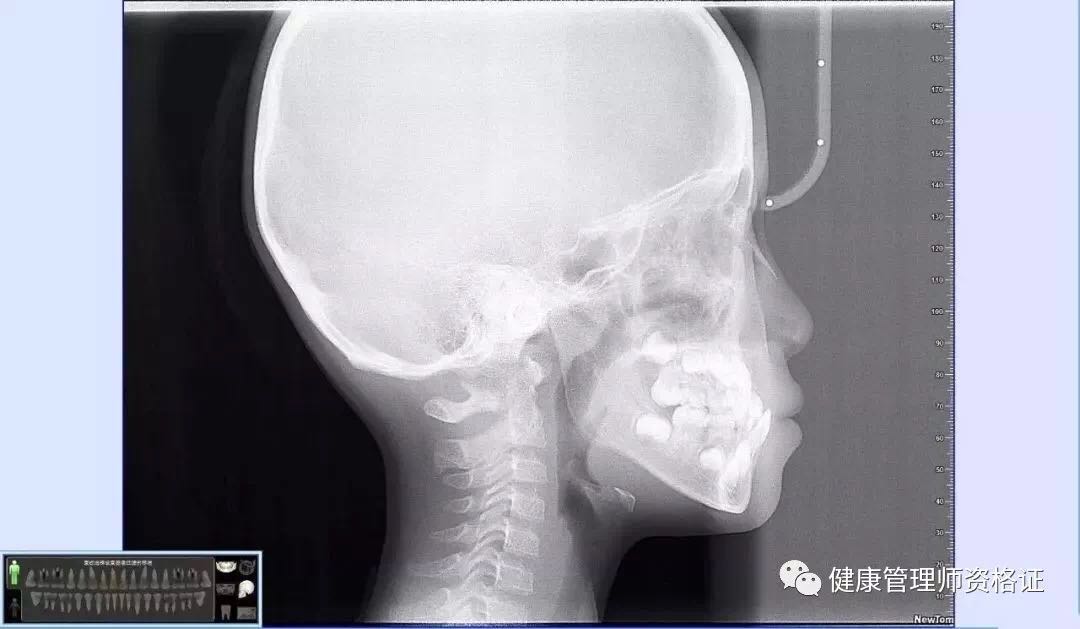

(2) 牙科頭顱側位片

可以展現牙齒及頜骨影像。可見孩子側面骨骼、上下頜骨發育 、氣道、腺樣體等各組織結構間是否影響孩子面型發育。

想要矯正牙齒的小朋友,以上兩項牙片一定要拍哦~